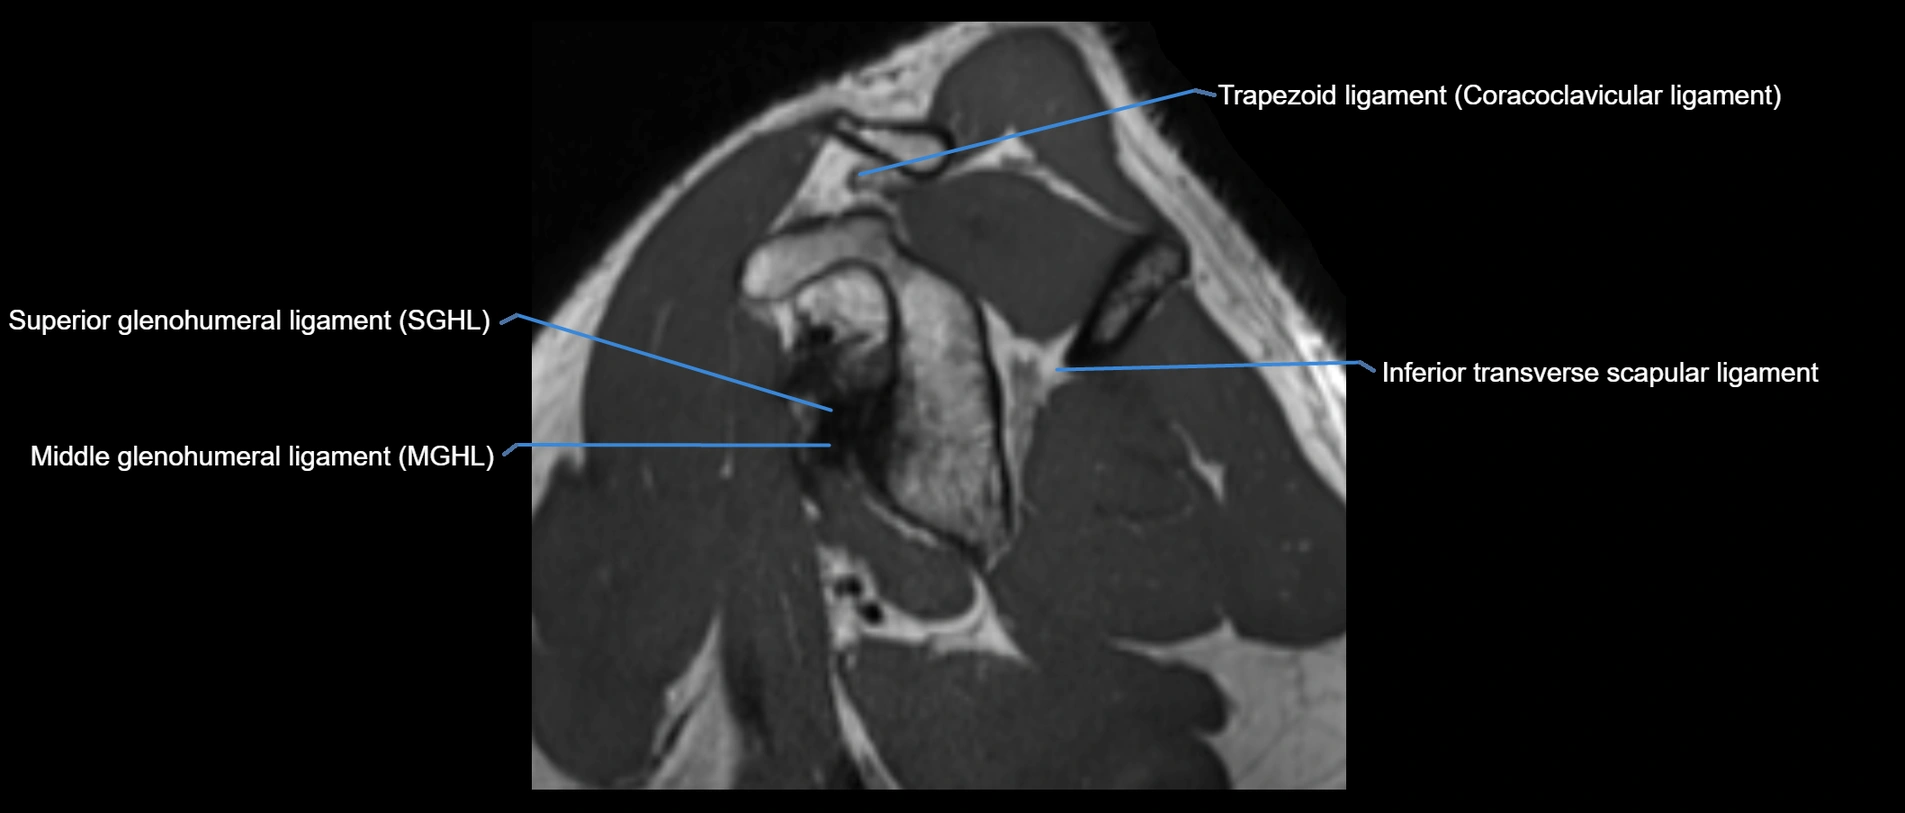

MRI images

image

MRI Appearance

• T2-weighted images:

• Proton Density Fat-Saturated (PD FS):

• Excellent for assessing joint capsule, coracoclavicular ligaments, and periarticular edema.